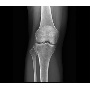

Klinikai esetek

Klinikai esetek 2.

Klinikai esetek 3.

Klinikai esetek 4.